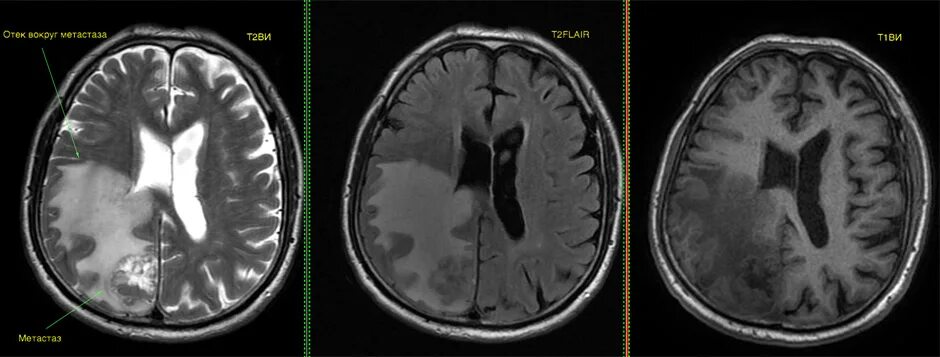

Отек головного мозга мрт